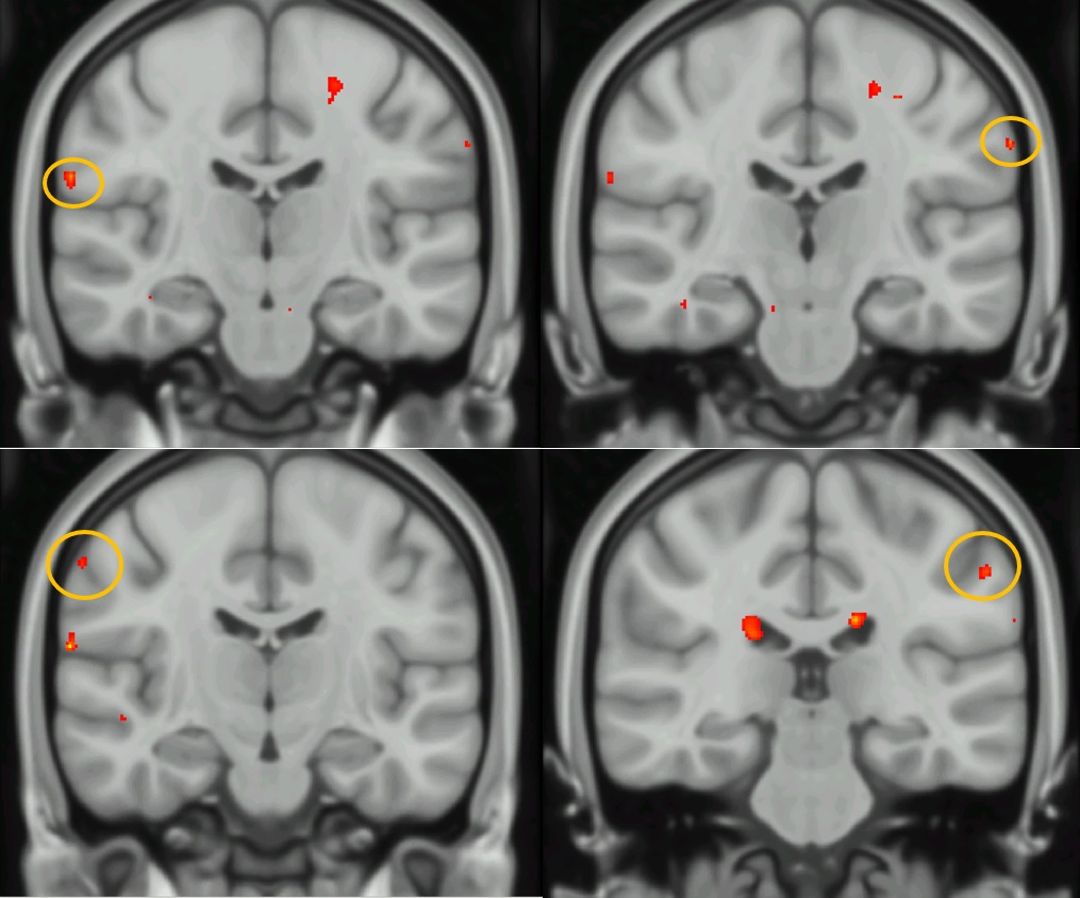

In S1, activation was seen in both the superomedial S1 and inferolateral S1 in both hemispheres during stimulation of the anus, perineum and clitoris (Figure 1). Of these, clitoris stimulation gave significantly bigger activation zones and more frequently in multiple regions of S1 simultaneously. Activation patterns during areolar stimulation in S1 were similar, however limited to the right hemisphere.

In our group analysis, we saw significant activation in S1 bilaterally during clitoral and anal stimulation, both in the inferolateral regions of S1 (Figure 2). No other stimulation regions saw significant activation in S1 (Figure 3). See Table 1 (Figure 3) for all significant clusters in group analysis.

Figure 1 Figure 1. Typical S1 activation patterns in individual participants. a) shows activation during electrical stimulation of the anus; b) of the left areola; c) of the clitoris; d) of the perineum

Figure 2 Figure 2. Activation in S1 for the group analysis during stimulation of the clitoris (top images) and anus (bottom images).